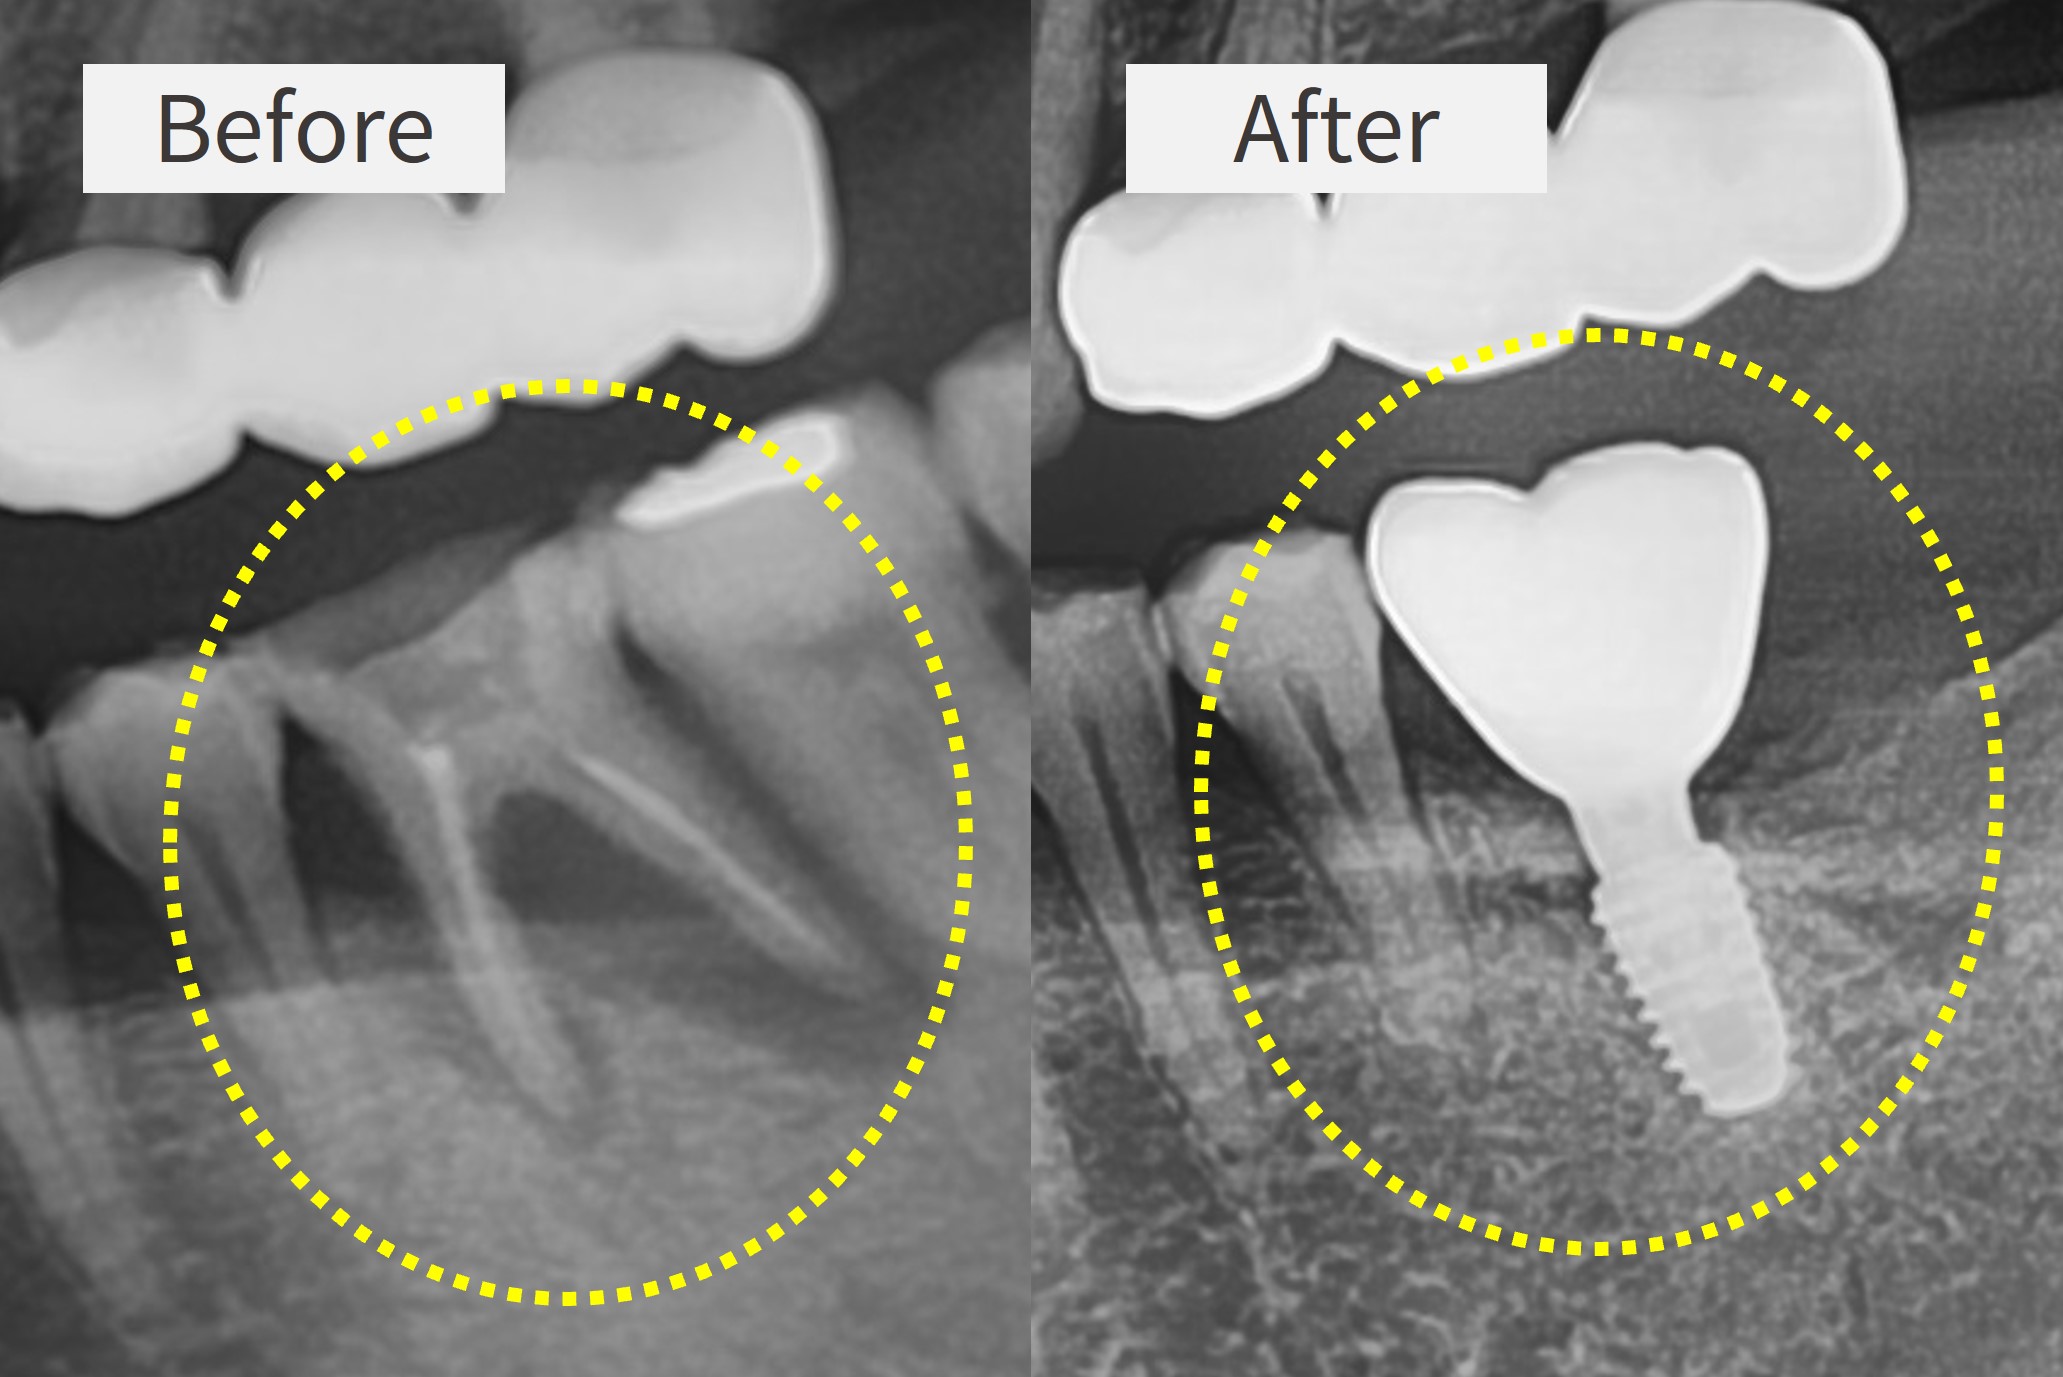

바로나은치과의원은 임플란트 교육을 하는 치과의사가 직접 진료하며, 3단계 무통마취 시스템으로 통증에 대한 두려움을 덜어드립니다. 고화질 카메라를 이용한 치료 전후 사진 비교를 통해 과잉진료 없이 믿고 치료받을 수 있습니다.